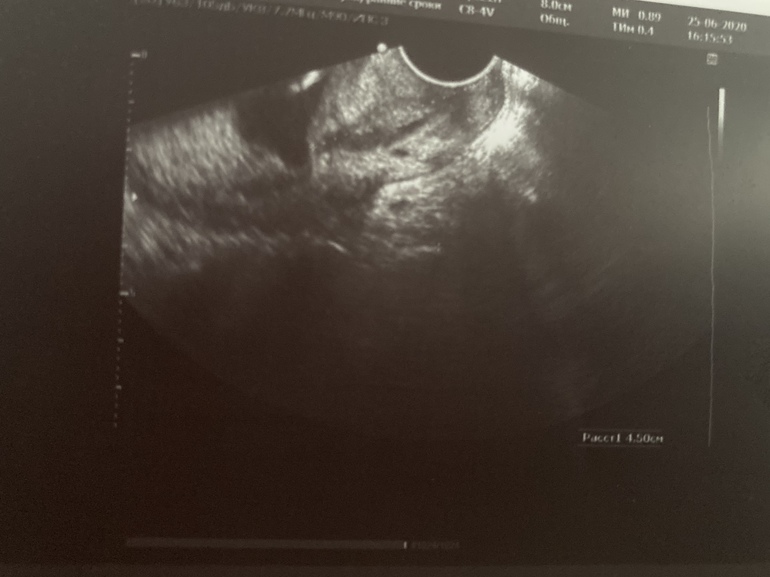

Девочки, может кто разбирается в Узи фото)

Была уже у трёх врачей и три разных мнения, кто говорит что внутренний зев приоткрыт, кто открыт, кто закрыт. Цервикальный канал расширен, но моя врач уверяет, что шейка длинная и всё нормально.. а кто-то прям панику разводит и говорит сильное расширение. Ничего не понимаю.

При закрытом зеве тонкая однородная полоска в шейке, у вас вроде как расширено, но не по всей длине... а сколько написали в цифрах?